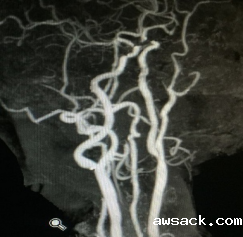

血管搭桥新技术治疗烟雾病

术前

术后

颈动脉内膜剥脱术(CEA)治疗脑缺血

术前           术后